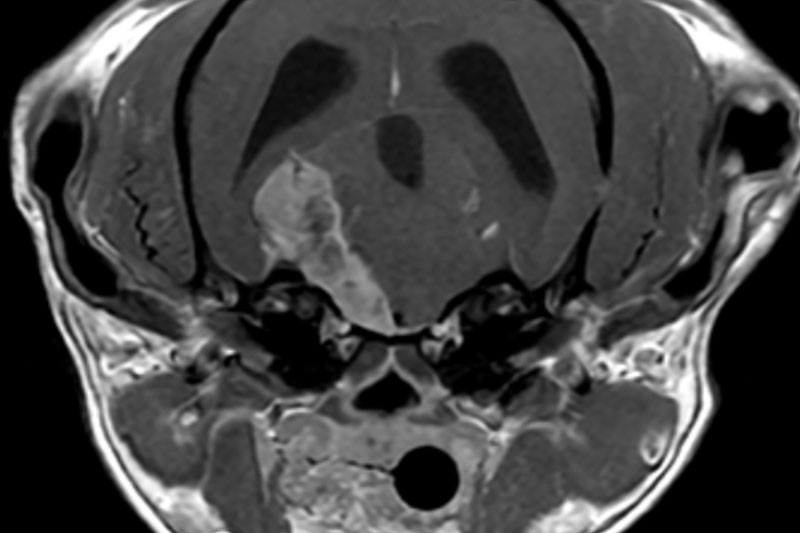

본 병원은 GE사의 1.5T 고해상도 자기공명영상장치(MRI)를 이용하여, 자기장을 이용한 비침습적 방식으로 뇌, 척수, 근골격계 등 다양한 연부조직을 정밀하게 영상화할 수 있습니다. MRI는 방사선을 사용하지 않아 반복 촬영에도 안전하며, 신경계 및 연부조직에 대한 탁월한 해상도를 제공하여 정확한 진단에 매우 유용합니다.

또한 본원의 MRI 장비는 GE사의 PROPELLER 기법을 도입하여 호흡이나 움직임에 따른 영상 왜곡을 최소화하면서도 검사 시간을 단축시켜, AI 기반 영상 처리 기술을 통해 노이즈를 줄이고 더욱 선명하고 명확한 영상을 획득할 수 있습니다. 이러한 기술적 강점을 바탕으로 마취 시간과 그에 따른 환자의 부담을 줄이면서도, 진단에 충분한 고화질 영상을 안정적으로 확보할 수 있습니다.